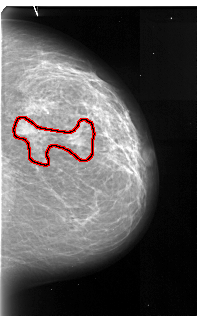

A_1056_1.LEFT_MLO

FILE: A_1056_1.RIGHT_MLO.OVERLAY

TOTAL_ABNORMALITIES 1

ABNORMALITY 1

LESION_TYPE MASS SHAPE IRREGULAR MARGINS ILL_DEFINED

ASSESSMENT 4

SUBTLETY 5

PATHOLOGY MALIGNANT

TOTAL_OUTLINES 1

BOUNDARY